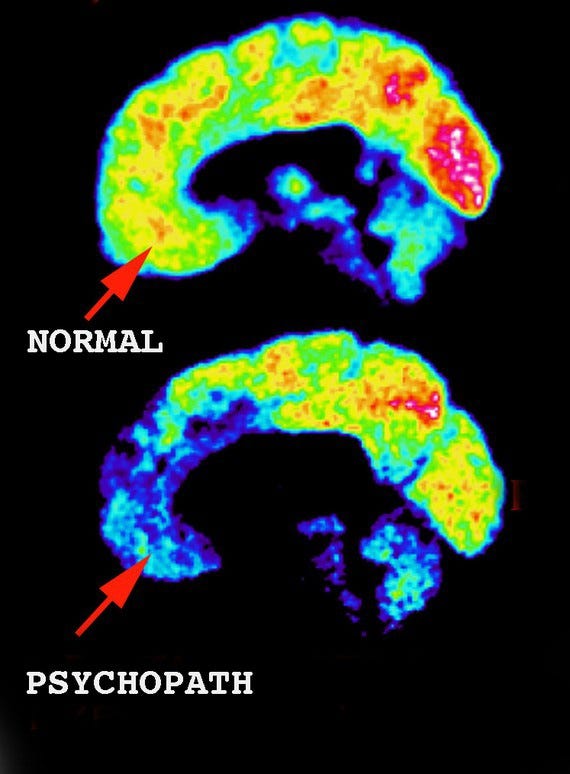

However, the same argument cannot be made for psychopathy. Psychopathy is genetic, it is not environmental. What changes in a psychopathic person based on environmental triggers is behavior, not the psychopathy itself. Regardless of how a psychopath is raised, they are born psychopathic, and psychopathy will remain. Environment and abuse can create a very badly behaving psychopath, but won’t make them more or less psychopathic. Scan the brain of a noncriminal psychopath, and you will see what I mean;

Sociopaths on the other hand don’t seem to have structural differences in the brain. Perhaps there are changes, but so far, that hasn’t been demonstrated. Due to this, sociopathy gets the shaft in terms of research. If you can’t point to something and say, “See, there it is”, no one wants to give you research money to look into it further. Psychopathy has differences that can be mapped, sociopathy so far, doesn’t.